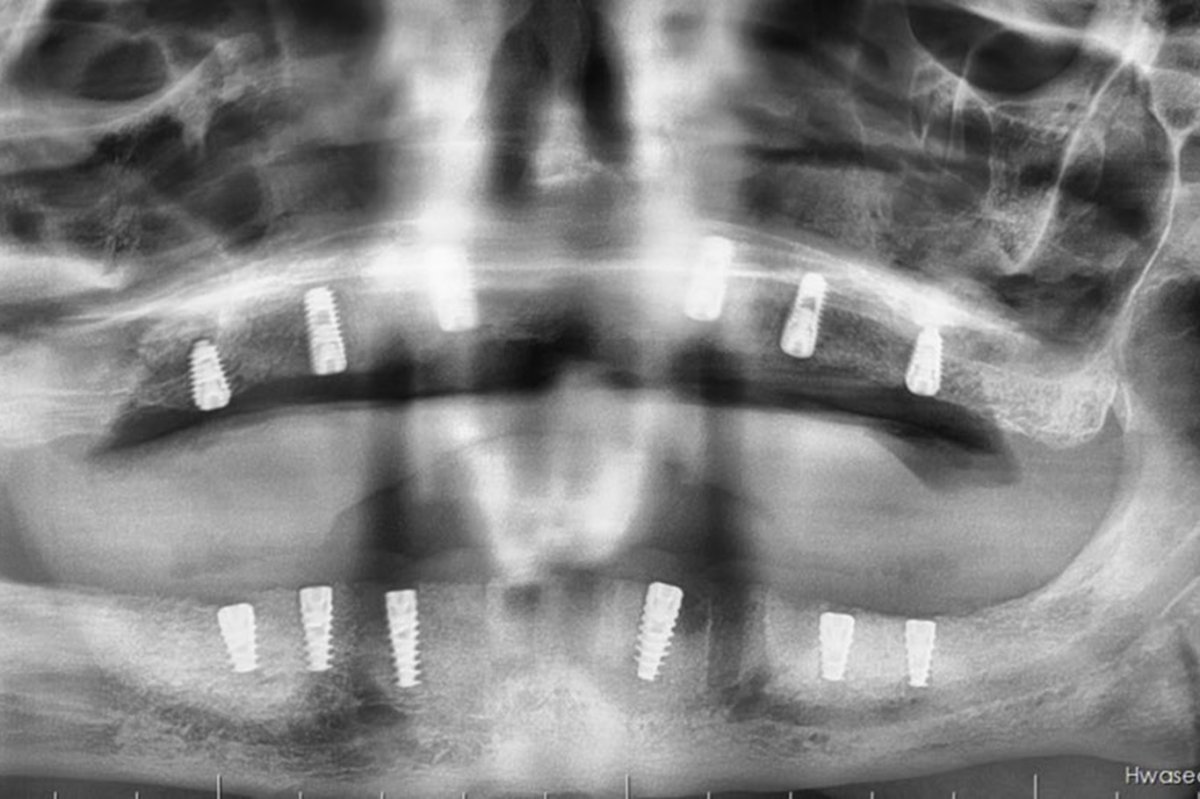

Hastanede tedavi gören 55 yaşındaki Hüsnü Üner’de sağ ve sol üst çene arka bölgelerinde ileri düzey sinüs sarkması ve kemik yetersizliği tespit edildi. Lokal anestezi ile tedavi edilmesi mümkün olmayan vakada, Ağız, Diş ve Çene Cerrahisi Uzmanı Uzm. Dt. Ebru Baydan Çol tarafından genel anestezi altında her iki üst çeneye aynı seansta açık sinüs lift ameliyatı uygulandı.

Cerrahi işlemin ardından hastanın üst ve alt çenesine implantlar yerleştirildi. Ameliyat sonrası genel durumu stabil olan hastanın iyileşme sürecinin planlandığı şekilde devam ettiği bildirildi.